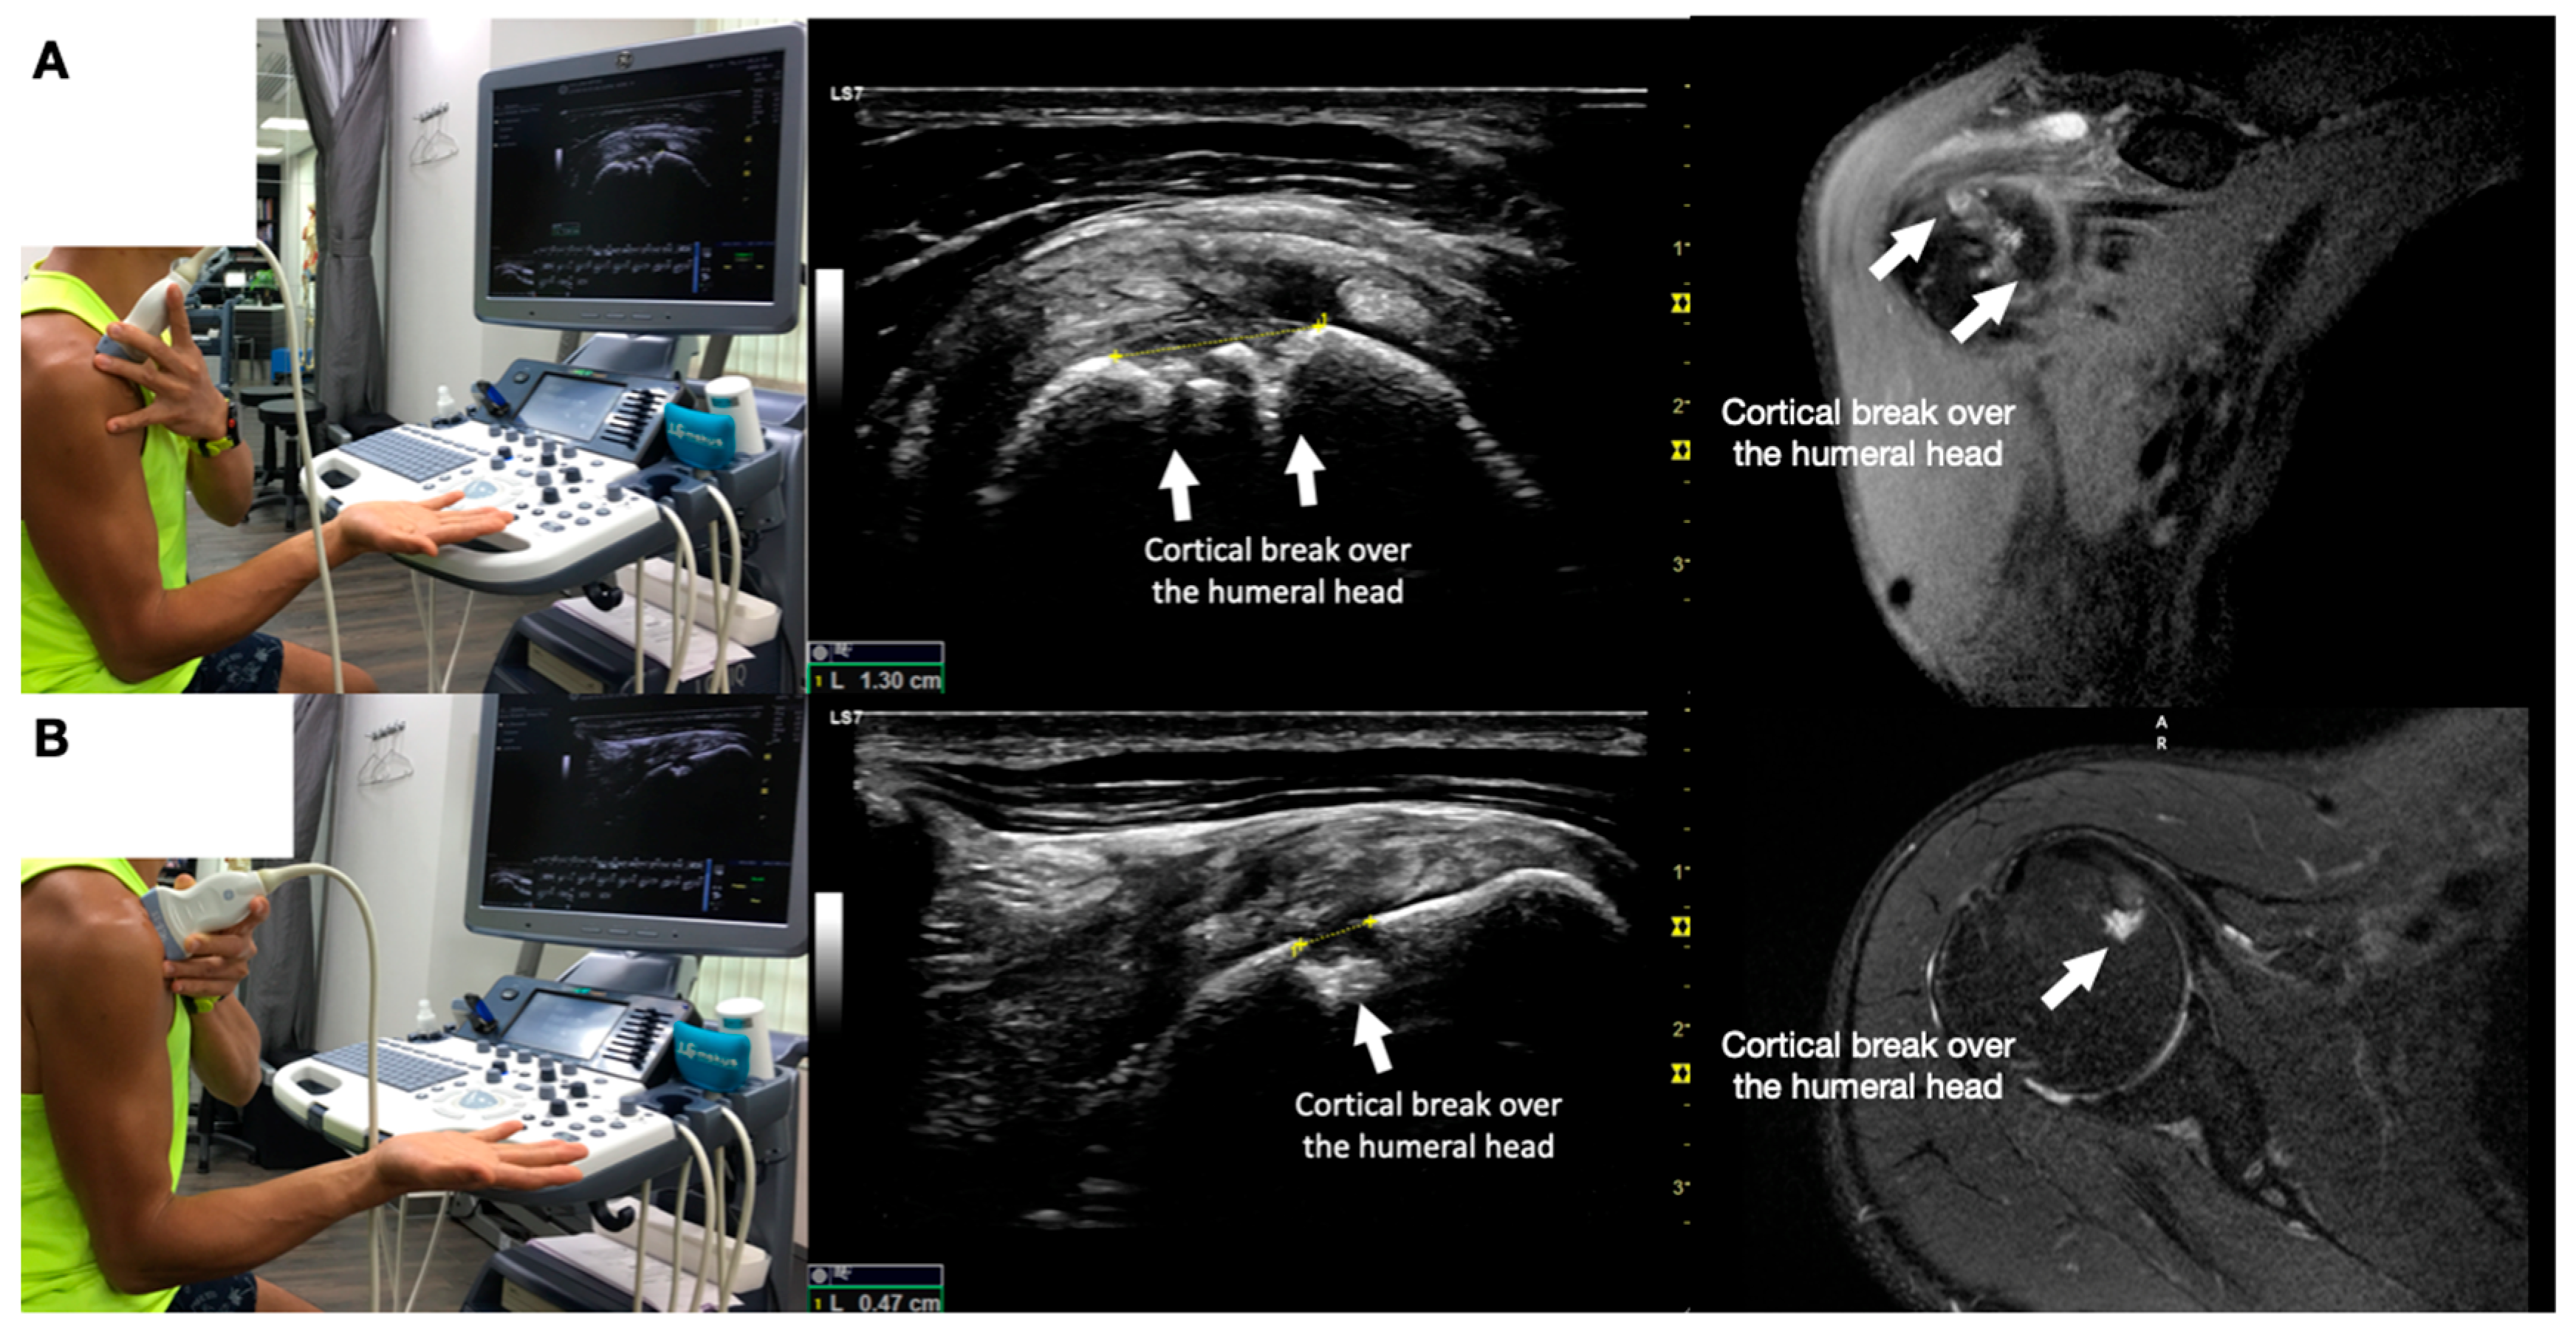

Figure 3.

Sonoanatomy of the lateral boarder of the scapular, its related muscles, and the infraspinatus fascia. Video S7 has demonstrated the step-by-step scanning techniques of these structures shown in this figure. Available online: https://www.dropbox.com/s/891m19vvw6bak34/Figure%203.docx?dl=0 (accessed on 1 January 2023).